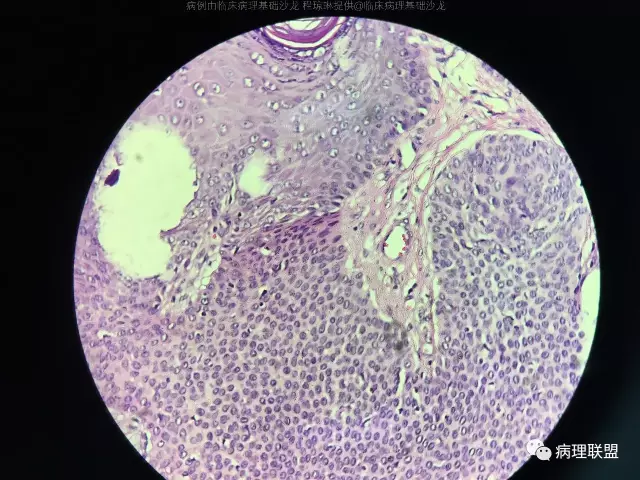

病例2 女,60,头部肿物

@左淑英 左老师,汗1考虑单纯汗腺棘皮瘤;汗2考虑色素性汗孔瘤。